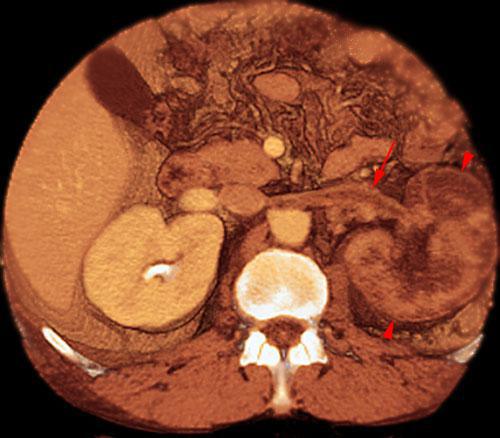

Síndrome del cascanueces retroaórtico